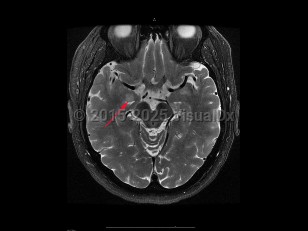

To distinguish encephalitis from other causes of encephalopathy, core components of the presentation of encephalitis include the presence of fever (within 72 hours before or after presentation), cerebrospinal fluid (CSF) pleocytosis (≥ 5 /mm3), or MRI or electroencephalogram (EEG) changes consistent with encephalitis.

Encephalitis is often secondary to a virus but may be caused by bacteria, fungi, or toxins. Three of the most common etiologic agents for acute encephalitis are viral including herpes simplex virus (HSV), varicella-zoster virus (VZV), and enterovirus. Alternatively, encephalitis can be caused by autoimmune conditions (anti-NMDAR encephalitis, lupus cerebritis) or inflammatory or paraneoplastic conditions, or be a consequence of stem cell transplant. Patients with encephalitis may also have concomitant meningitis (meningoencephalitis).